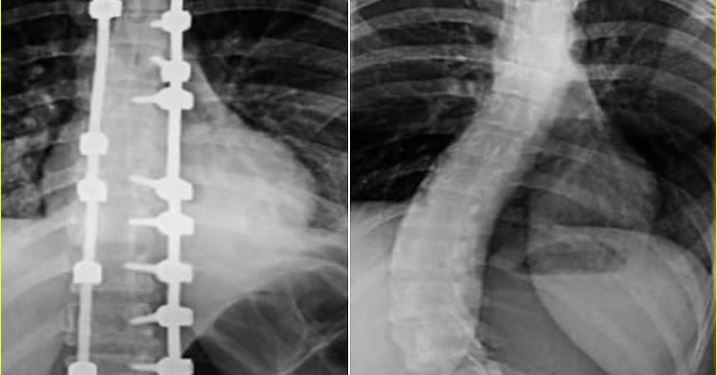

تمكن فريق طبي متخصص في مستشفى الدكتور سليمان الحبيب بالصحافة، من إجراء عملية جراحية ناجحة لتقويم تشوّه متقدم في العمود الفقري لشابة عشرينية، كانت تعاني من ميلان (جنف) بنسبة 55% وتحدب صدري بمقدار 70 درجة، ما أثر على قدرتها على الجلوس والمشي بشكل مستقيم وأصاب حياتها الاجتماعية والنفسية بالإجهاد.

وذكر د. تركي العنزي، استشاري المخ والأعصاب وجراحات العمود الفقري المعقدة ورئيس الفريق الطبي، أن المريضة خضعت فور وصولها للمستشفى لفحوصات دقيقة، شملت الأشعة السينية والرنين المغناطيسي، والتي أظهرت الحاجة لتدخل جراحي عاجل لتصحيح الانحناءات وتحسين المظهر الخارجي للظهر.